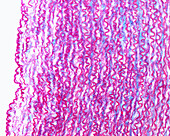

13742427 - Elastic artery, light micrograph

13742425 - Elastic arteries, light micrograph

13742428 - Elastic artery, light micrograph

13742426 - Elastic arteries, light micrograph

13218770 - Elastic artery, light micrograph